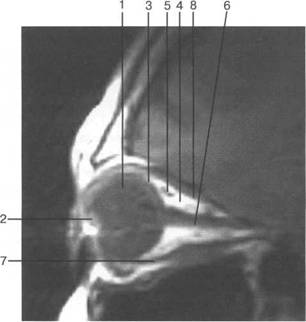

opticus).

(a. ophtalmica).

HU), каплив 121h711b ают контрастный препарат. Толщина хнюю прямую мышцу видно плохо, обычно ее изображение слив 121h711b ается с изображением мыш­

На КТ-изображениях глазное яблоко имеет шаровидную структуру, четко выраженную обо­лочку, внутри его определяется хрусталик эллиптической формы размером 4x9 мм, плотностью

(corpus ciliare), (zonula ciliaris)

При сонографии отчетлив 121h711b о выявляется чивается хрусталиком, а сбоку - ресничным

четлив 121h711b о дифференцировать зрительный нерв и глазодвигательные мышцы (рис. 2.16, 2.17).

нии 10-15 мм от склеры (рис. 2.21,